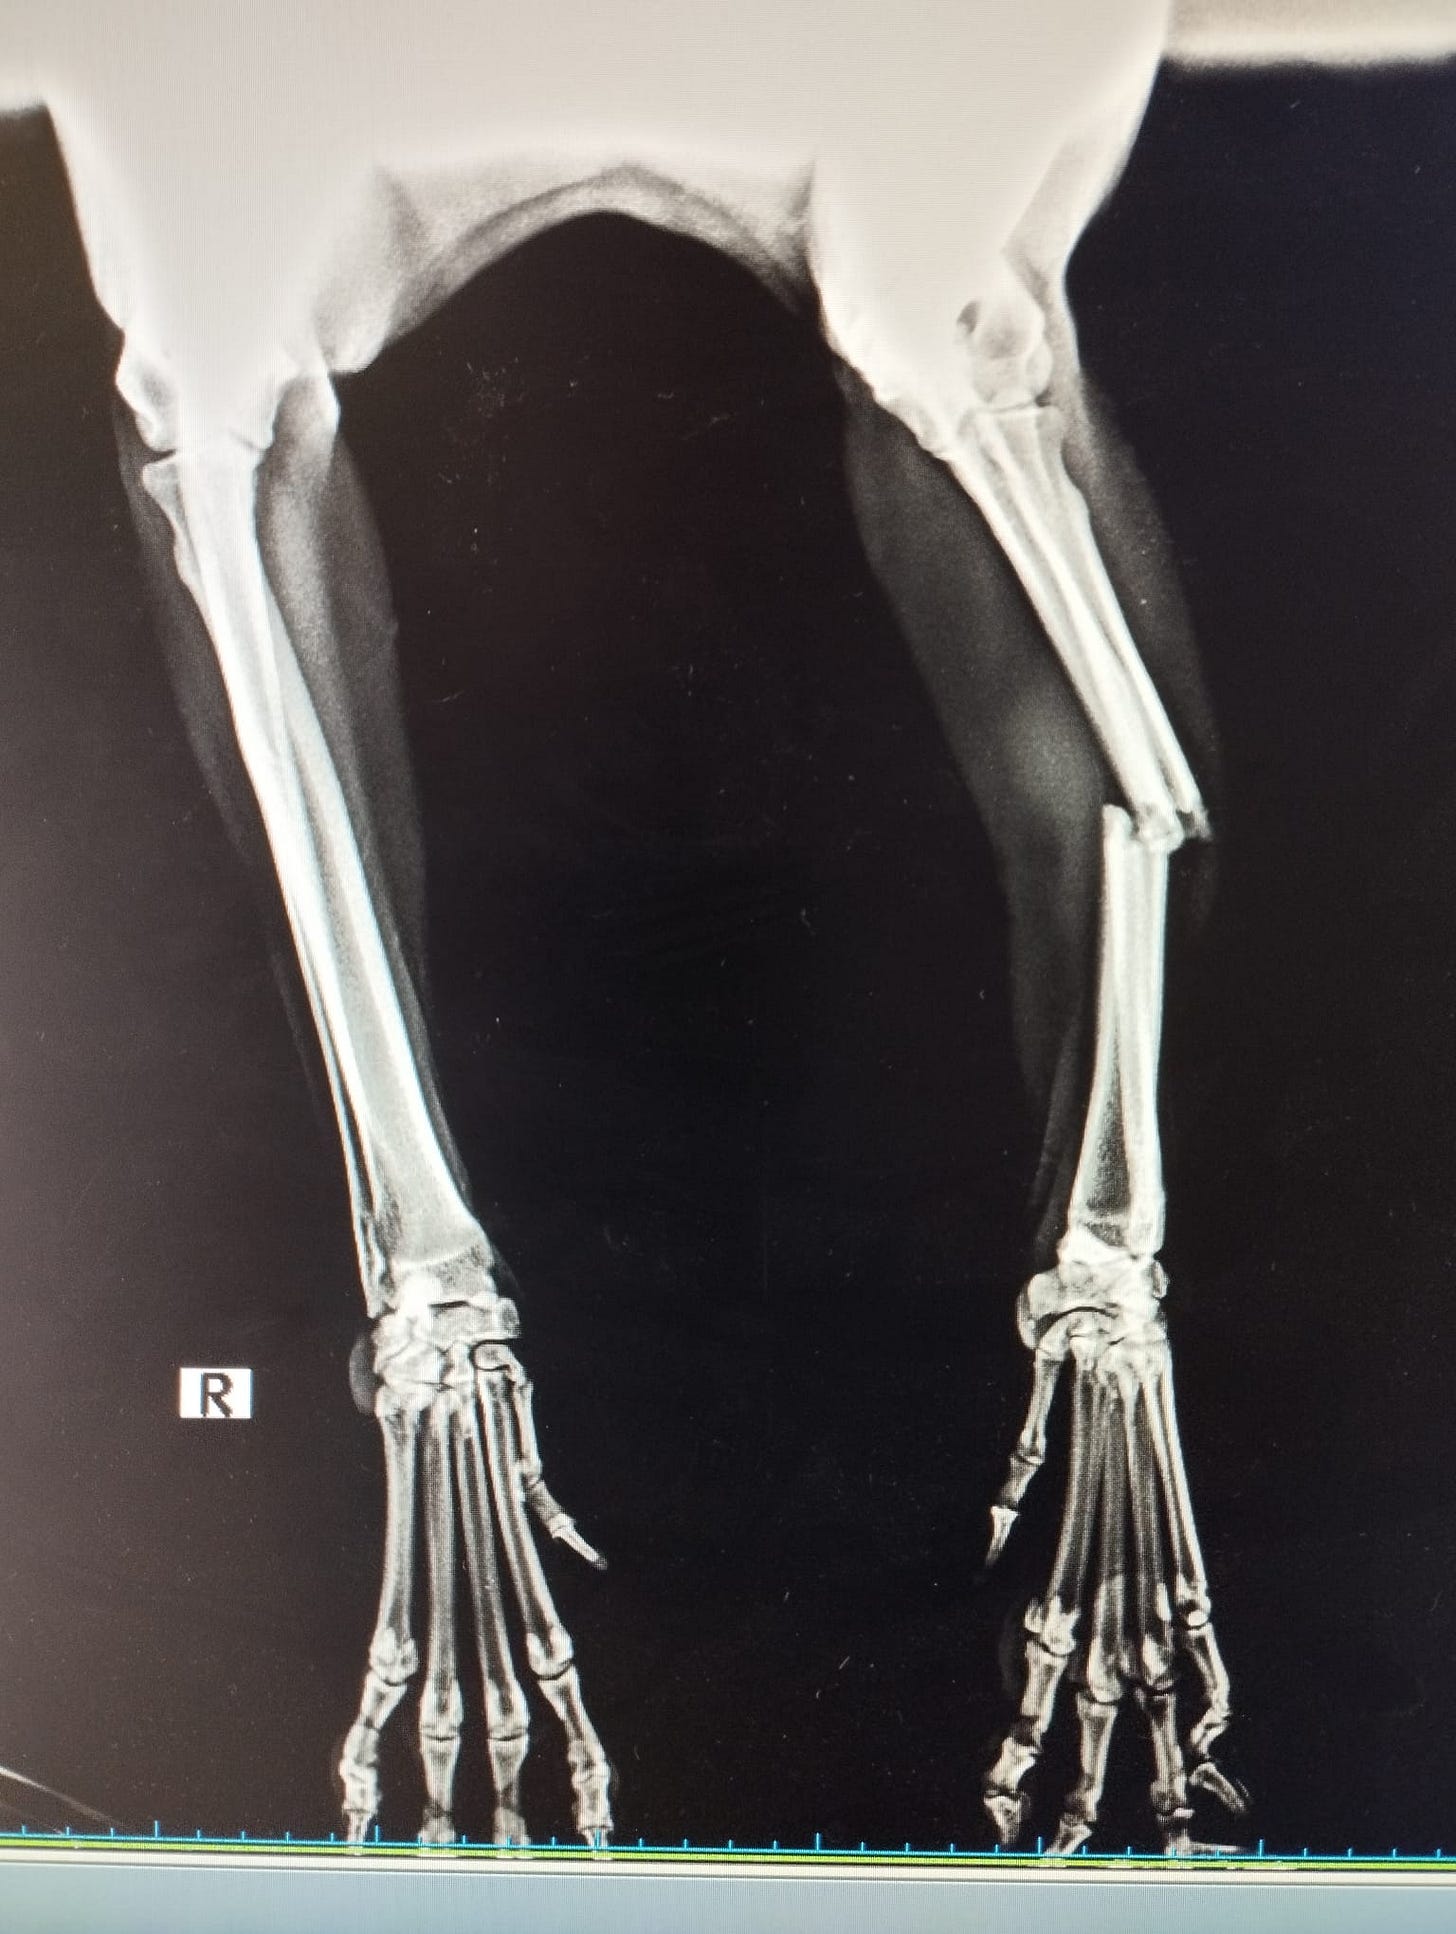

Apollo was examined & found to have a nasty break in his forearm which needed to be repaired by osteosynthesis, a surgical procedure which joins broken bones back together with plates.